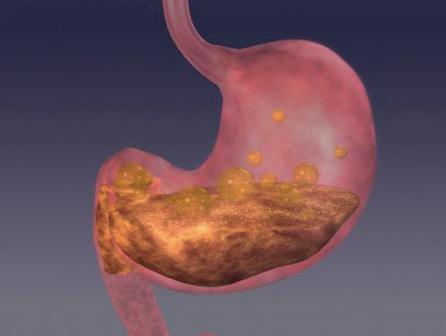

5,其他疾病:胃石症,胃底静脉曲张,胃内异物等"胃超声造影"适宜人群1

胃潴留是什么?日常预防胃潴留的6个方法,赶紧收藏!

您是否知道什么胃潴留?